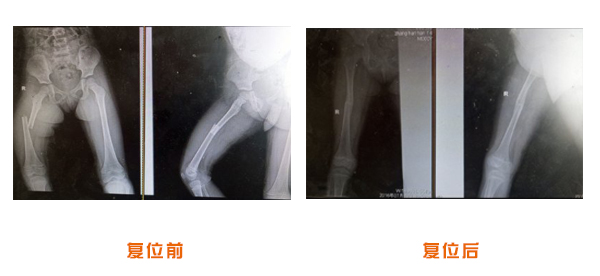

肥城市安駕莊梁氏骨科醫院是一所以梁氏手法正骨配合膏藥為特色的現代化??漆t院。

梁氏骨科術始創于清雍正年間,歷經八代,至今已有三百年歷史。據1929年泰安縣志載“梁瑞圖先生,字增生,號蓮峰,安駕莊人,精岐黃并發(fā)明接骨,凡跌打車凡跌打車軋皮不破而碎骨者......【詳細】 |